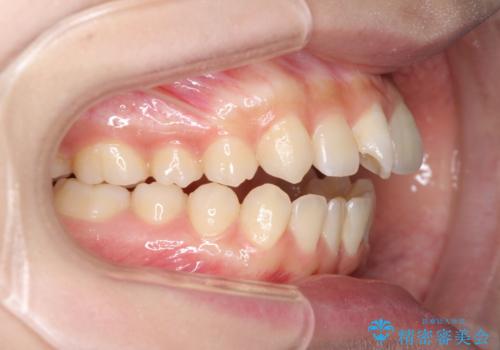

話しにくいオープンバイト ワイヤー装置による抜歯矯正治療

- 前歯のオープンバイトを気にして来院された患者様です。

上下前歯の前後位置が大きくずれていたため、上顎左右第一小臼歯2本を抜歯してワイヤー装置による矯正治療を行うこととしました。

オープンバイトの原因は舌の突出癖であり、癖が改善されないと治療経過に影響を及ぼすため、舌のトレーニングを指示しました。